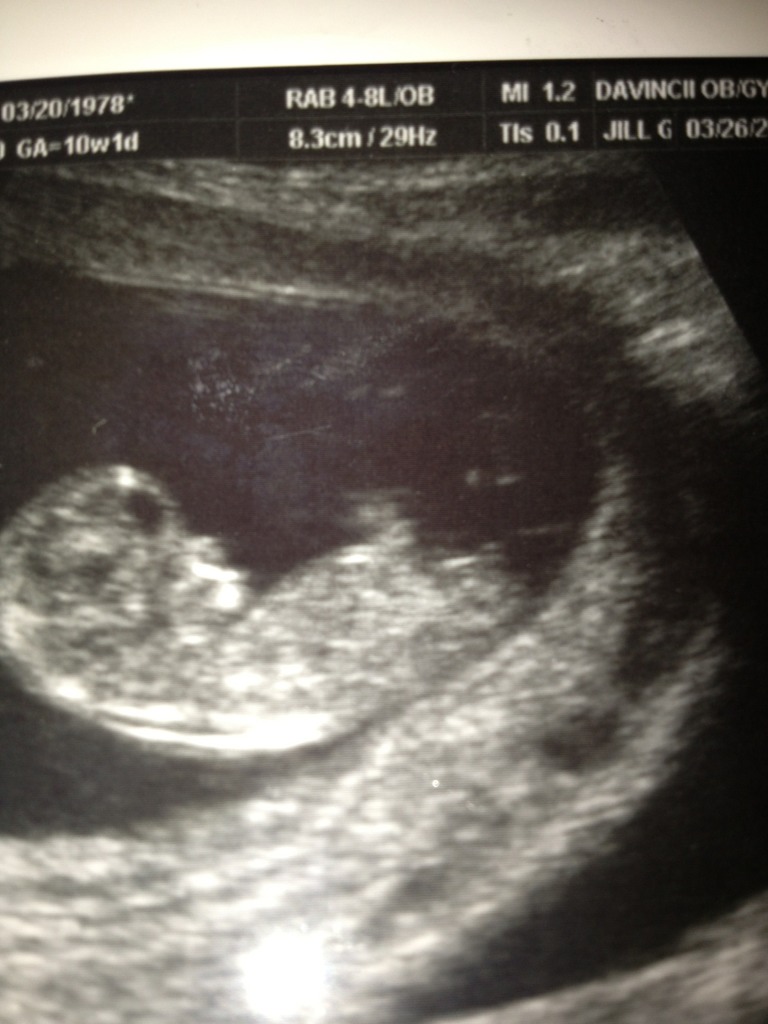

I am only 10.4 but tech said baby was measuring more like 11weeks. Anyways any nub/skull guesses or too early?Attachment 9937Attachment 9938

Yup too early... Any guess would be 50/50

first one looked like a boy nub that hasn't risen, the second one looked like a girl nub. I agree, too early either way. probably better around 12-13 weeks!

Maybe girl? But very early.